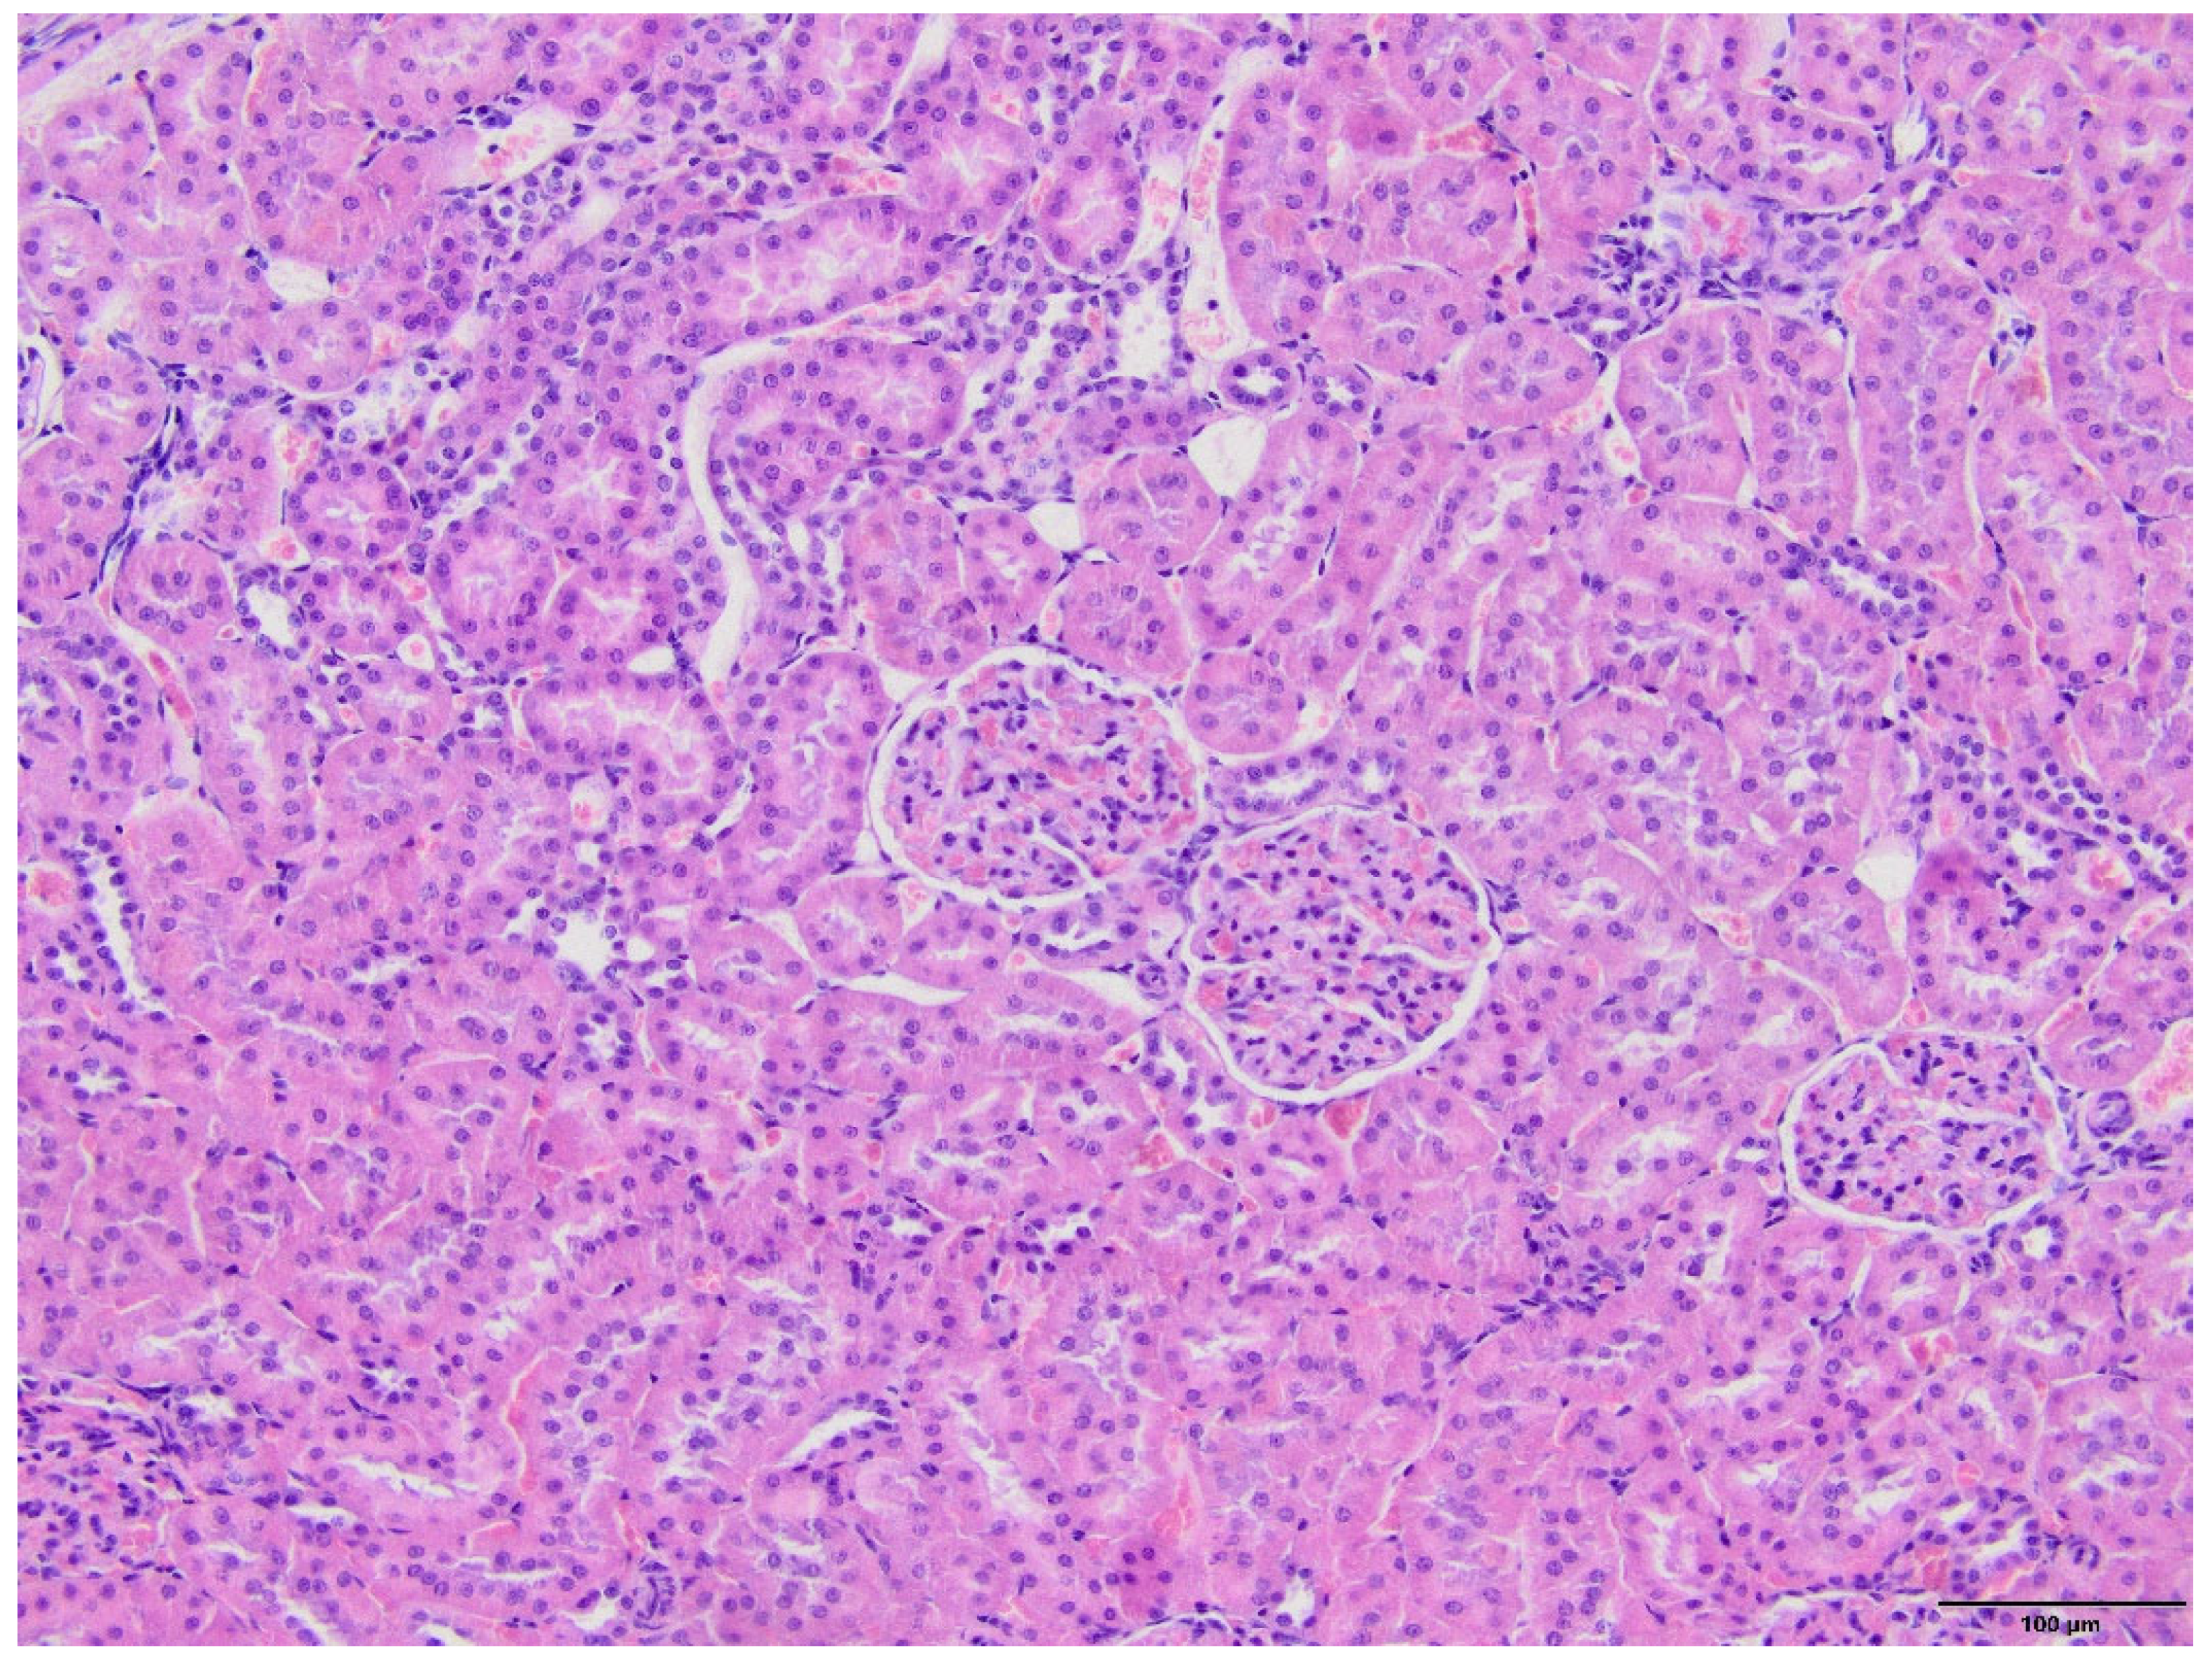

2.4. Kidney Histopathology